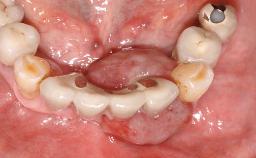

This case describes the ongoing management of a 64-year-old healthy, non-smoking female patient with erosive oral lichen planus (OLP) affecting the gingivae and the buccal and lingual mucosa. The peri-implant mucosa was also affected subsequent to implant placement. The patient had osseointegrated implants (four in the maxilla, four in the mandible) placed following extraction of hopeless teeth and a healing period. The patient had a history of OLP prior to implant placement and had been referred to an oral-medicine specialist for definitive diagnosis and treatment. She exhibited generalized oral mucosal involvement. Following a clinical assessment, biopsy, and blood tests, she was treated with topical corticosteroids. Systemic prednisolone was reserved for severe flare-ups. Amphotericin lozenges were used in combination with corticosteroid treatment to prevent the development of oral candidiasis.